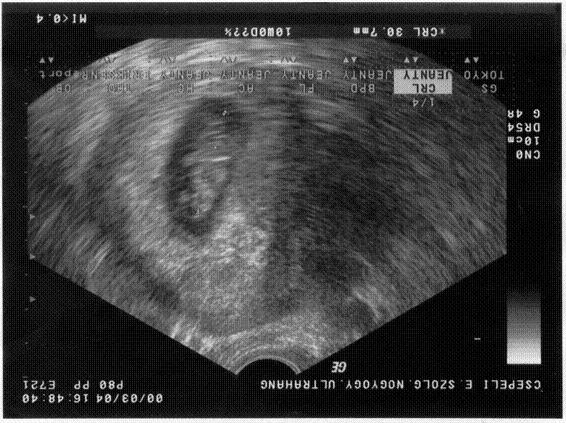

30. heti poci